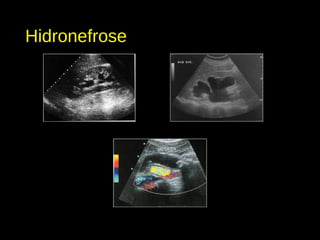

Hidronefrose

• É papel do ultrassonografista evidenciar se o quadro é agudo ou crônico.

Aguda Crônica

Dimensões renais Normais ou aumentadas Geralmente reduzidas

Parênquima renal Geralmente normal Afilamento focal ou global

Sistema pielocalicial Dilatação sem alteração

morfológica

Baqueteamento/distorção do

sistema calicial

Ecogenicidade cortical Geralmente normal Hiperecogenicidade difusa

Urotélio Geralmente normal Normal ou espessado

• Classificação ultrassonográfica:

• Leve: dilatação da pelve renal e/ou grupamentos caliciais, em grau inicial.

• Moderada: dilatação mais evidente da pelve e cálices, sem alterações associadas do

parênquima renal.

• Acentuada: dilatação global do sistema pielocalicial, associada a afilamento da cortical

renal.